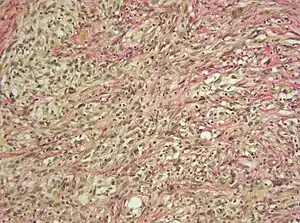

| Micrograph showing a gliosarcoma. Elastic van Gieson's stain. | |